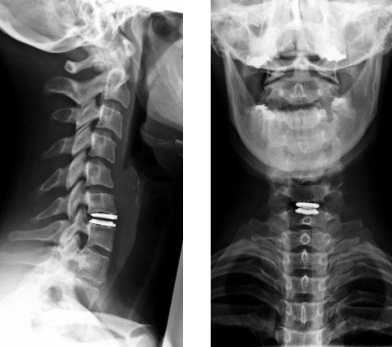

Укладка при рентгенограмме шейно-грудного перехода в боковой проекции (по методу Твайнинга, в позе пловца)

Рентген шейного отдела позвоночника имеет целый ряд особенностей. Выполняться процедура может в нескольких проекциях, а именно:

Полную протяженность шейного отдела позвоночника можно увидеть только в положении сбоку. Если же снимок делается в прямой проекции, тень от нижней челюсти будет закрывать первый и второй позвонки. Чтобы получить качественное изображение, потребуется сделать прицельный снимок через открытый рот пациента.

Как правило, назначается процедура рентгена шейного отдела позвоночника в двух проекциях - боковой и прямой. Дополнительно может назначаться косая, если нужно детально рассмотреть межпозвонковые отверстия.

То, как будет проводиться процедура, зависит от проекции, в которой выполняется снимок. Могут быть такие проекции:

- прямая - пациент лежит или стоит прямо, руки вдоль туловища, рентгеновский луч направляется под углом в 15-20 градусов на щитовидный хрящ и проходит через шею;

- боковая - пациенту нужно встать боком и слегка приподнять подбородок, также процедура может выполняться лежа;

- рентген шейного отдела позвоночника могут делать через рот - это разновидность прямой проекции, позволяющая увидеть верхние шейные позвонки;

- косая - назначается редко, предназначена для изучения межпозвоночных отверстий.

Рентген шейного отдела позвоночника в двух проекциях

Чаще всего процедура выполняется в обычной прямой и боковой проекциях. Как правило, такого исследования достаточно, чтобы оценить состояние позвонков и определить причину жалоб пациента. По получении снимков могут быть назначены дополнительные исследования, которые позволят оценить состояние мягких тканей шеи, либо же будет прописано лечение, если информации окажется достаточно.